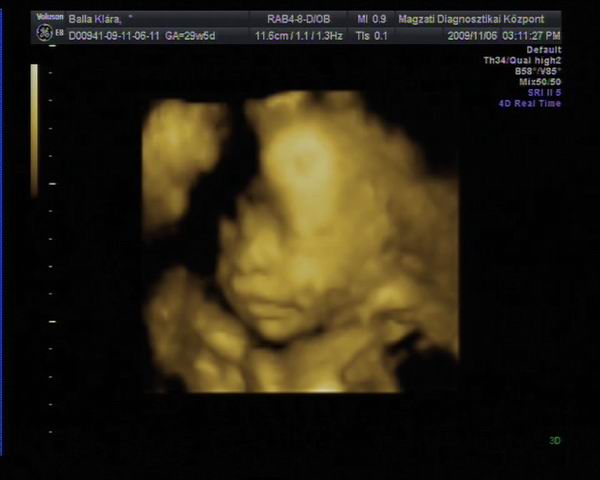

Athena, Jutka. Nilszi-nek igaza van abban, hogy sokszor nem mérnek pontosan az UH-k alkalmával. Misem bizonyítja ezt jobban , mint az én esetem. Szerdán este a rendeléses Uh-n , ahol elég lelkiismeretesen mért a szonográfusnő, ott a picur méretét: 1518g-ra becsülték ( kicsit meg is ijedtem!) A pocakja szép nagy volt AC:255mm a combcsontja, amire kétszer is rámért FL:53mm, BPD( fejátmérő):75mm HC ( fejkörfogat):266mm.

Másnap reggel mentem 4D UH-ra, ahol BPD: 72,6mm HC: 261,9mm AC: 220,2mm FL: 57,5mm becsült súly: 1108g.

Pedig ugyan arról a gyerekről van szó!!!! Nem hiszen, hogy lüktetne a pocakomban. :lol:

Hát ennyit a gépekről és a pontos méretekről!!!

Ráadásul képzeljétek hogy jártam a 4D UH-n. Zsomborka egyáltalán nem akarta megmutatni magát, nem fordult be a gerincem felé néz és annyira betakarta a karjával és a felhúzott lábacskáival magát, hogy semmit nem lehetett látni belőle. Hiába forogtam, mozgattuk a pocakom, fel sem ébredt és egyáltalán nem akart elmozdulni.

Egyetlen képet tudott csak készíteni a szonográfus, azt is csak a talpacskájáról. Nagyon csalódott voltam, mert ugye azt már tudtam, hogy egészséges nincs semmi baja, mert azt már előző nap megnézték, most csak őt szerettük volna látni. Így nagy nehezen kikönyörögtem, hogy nem jöhetnék-e vissza, hátha fordul egy kicsit. Kora délutánra kaptam még egy időpontot. Persze mondanom sem kell, hogy otthon még bukfenceztem is, hogy egy kicsit elforduljon, csokit ettem, kávét ittam ( pedig soha nem iszom )

A babóca mégsem akart elmozdulni, már majdnem azt mondta a szonográfus, hogy csinál egy képet, de hagyjuk a DVD-t mert most sem látszik semmi, mikor egyszer csak mintha halotta volna Zsimbi mégiscsak fordult egy kicsit, hogy végre szülei megcsodálhassák. Persze a kép szemcsés volt és még így is betakart a kis kezecskéje egy kicsit, de mi olyan boldogok voltunk, hogy végre látunk belőle valamit, hogy madarat lehetett volna fogatni velünk. Sőt még ásított is egyet, biztos érezte, mekkora a sikere, annak, ha kicsit produkálja magát. Így végre meg lett a várva várt DVD. Sajnos képet nem tudok róla berakni, mert a laptop-om nem szereti ezt a DVD-t és nem akarja elindítani, így csak a lejátszónkon tudom megnézni, de ott nem tudok képeket kivágni. Így csak egy képet tudok bescannel-ni, amit az Uh-osok nyomtattak ki fekete fehérben.

Kép Zsomborka 28+4

Kép Zsimbi talpacska